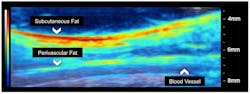

This image shows how dual-modality ultrasound and photoacoustic tomography can “see” structural information such as blood vessels, in addition to compositional information such as fat deposition.

Among other potential uses for photoacoustic tomography is mapping of lipid deposition within an arterial wall that can cause other health problems, and measuring cardiac tissue damage and tumor biopsies. Using photoacoustic tomography for intraoperative tumor biopsies could help surgeons ensure they remove all the cancer from a patient.